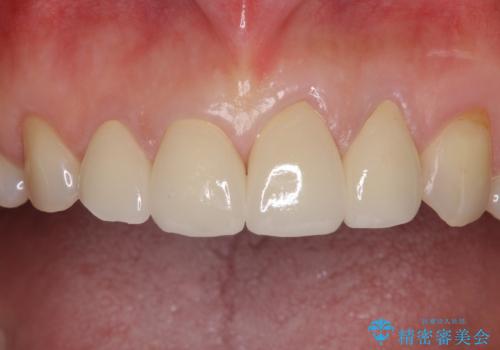

4本の前歯が気になっていたので、全てをオールセラミッククラウンにて補綴治療を行うこととしました。

4本とも治療前の歯髄の状態は正常でしたが、補綴治療により歯を大きく削ることになるため、歯髄が炎症を起こすリスクがあることを了解いただきました。

口元への目線ばかりを気にしていた状態から、自然な口元へと変貌し、患者様には大変満足していただきました。